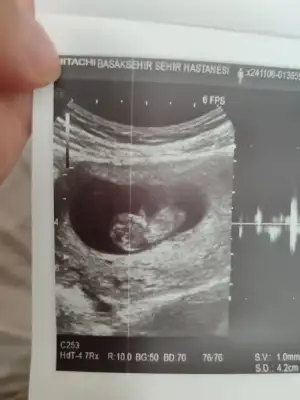

Ben bir şey sormak istiyorum. Siz benden önde olduğunuz için daha tecrübelisinizdir. Sat 26 Eylül haziran sonu temmuz başı doğum gözüküyor. Bugün tam 7.haftamız devlet hastanesinde karından ultrason ile bebeği zor gördü ve kalp atışını dinletmedi 4 mm dedi. Ben hem devlet hem özel takipli gidiyorum geçen hafta 6+2 de özelde alttan bebek gözüktü kalp atışını duyduk bebek o zaman da 4 mm di. Sorum şu karından ve altttan bakıldığında ve cihazlara göre bu farklılık olur mu yoksa bebek gelişmemiş mi sizce cumartesi özelde de kontrolüm var ama içim içimi yiyor. Bu arada devlet şu an 6+1 dedi

Kesinlikle katılıyorum. Devlet hastanesine tahlillerimi yaptırmaya gidiyordum. Bana kese boş denildi. Yani kahrolmuştum. Bir kaç gün sonra kendi doktoruma gittiğimde dolu olduğunu gördük. Devlet hastanelerinde kullanılan cihazlar eski. Kalp atışı sesini bile dışarı vermiyor çoğu.